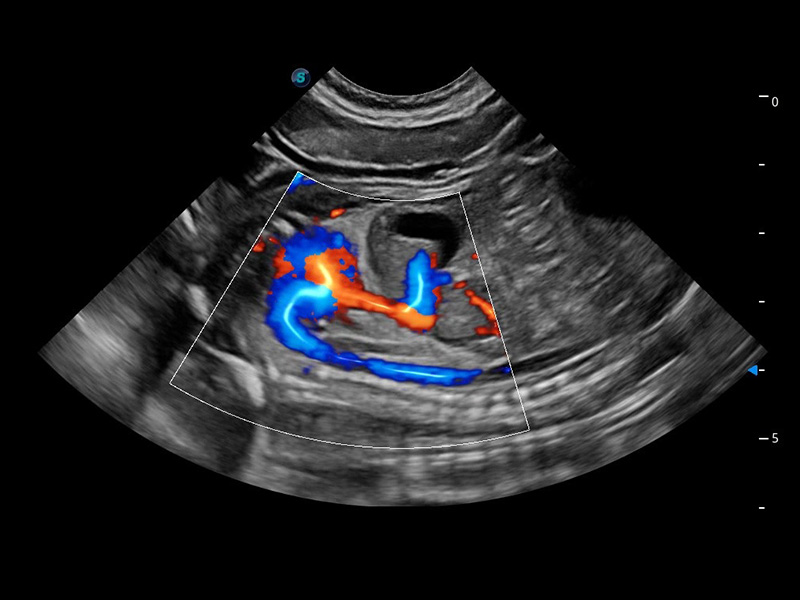

ProPet 60 作为一款高端台式动物超声设备,为动物医生的日常诊断提供了一系列贴合动物临床需求、解决临床实际问题的高级成像功能。凭借全系列高清探头,满足医生对腹部、心脏、生殖、浅表、肌骨等成像的所有需求,切实帮助您提升检查效率,提高诊断信心。

兽用彩色多普勒超声诊断系统

动物是人类最亲密的朋友和最值得信赖的伙伴。乐玩lewin国际也一直致力于探索动物专用的超声影像解决方案。 全新推出的ProPet系列,是乐玩lewin国际在动物超声影像智能化、专业化、精准化的一次跨越式革新。动物不能用言语来表述自己的不适,通过超声影像,ProPet系列搭建了动物医生与不同物种沟通的“桥梁”,为动物医生注入了“治愈之力”。